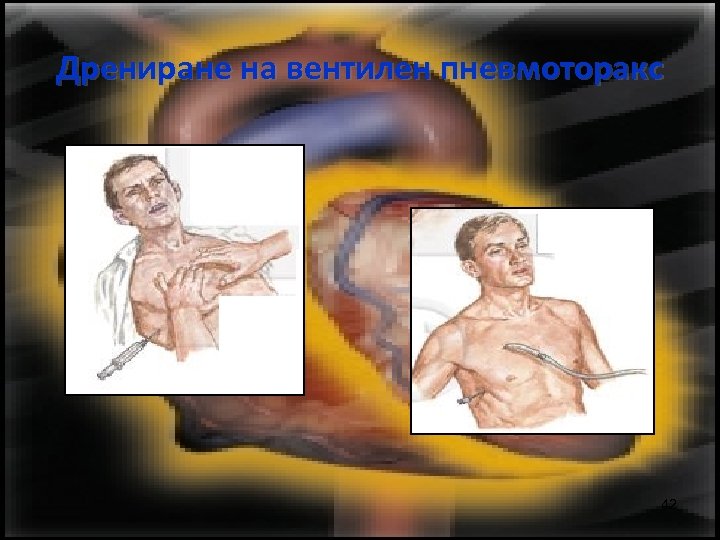

Дрениране на вентилен пневмоторакс 40

Дрениране на вентилен пневмоторакс Второ междуребрие Ключица 41

Дрениране на вентилен пневмоторакс 42